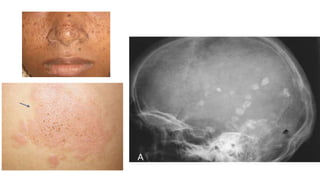

TUBEROUS SCLEROSIS

• The classic clinical triad consists of mental retardation, epileptic

seizures, and skin lesions

• Mc skin lesion is Adenoma Sebaceum(hamartoma)

-Others- Café-au-leit macules, Shagreen patches, gingival and peri-

ungual fibroma, skin tags

• Intracranial abnormality- Intracranial calcification in basal ganglia and

periventricular region

-Subependymal and cortical tubers

• Visceral abnormalities- myolipomas, angiomyomas, angiofibromas,

adenomas, or rhabdomyomas

Skeletal lesions- Irregular subperiosteal new bone

formation, ; well defined cysts in phalanges